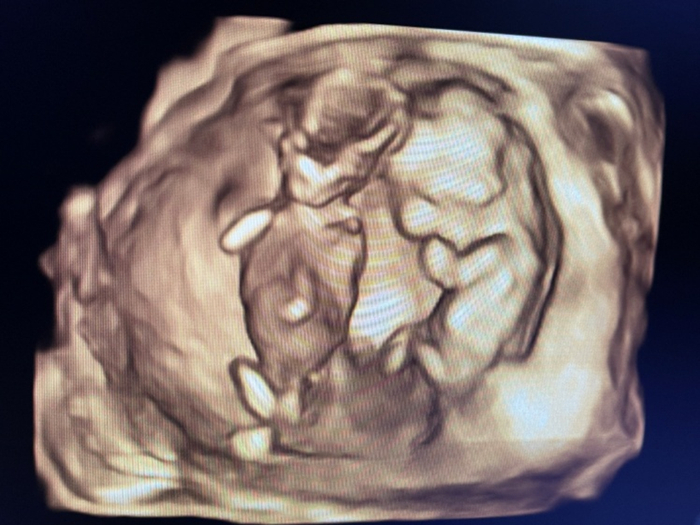

得知意外怀上三孩时,27岁的邱可整个人都蒙了。大脑的第一反应是不要——她的前两胎都是剖腹产,儿子三岁,女儿才刚满八个月。瘢痕子宫三剖难度大、风险高。

纠结随之而来。她开始寻找各种蛛丝马迹,试图将其解读为上天的安排。老二出生于2021年5月31日,也就是三孩生育政策官宣当天。襁褓中的孩子甚至还用手指比划了一个“三”,被邱可老公拍了下来。

对于另一些家庭来说,三孩更像是一场“美丽的意外”。吴薇检查出双胞胎时,也曾考虑过减胎手术,即在孕早期通过B超引导,用穿刺针吸出胚胎组织。作为一名妇产科医生,她曾见证过不少病人减胎,但轮到自己时,心里总有点舍不得。“他们俩像是上天的礼物,国家也鼓励多生。”